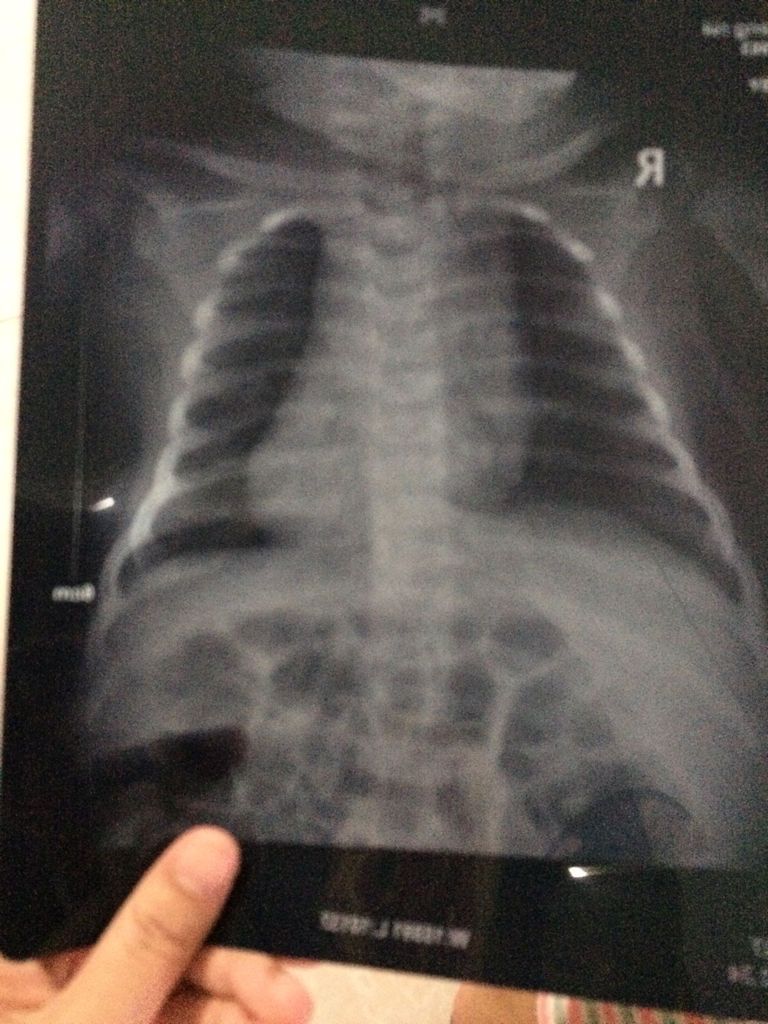

宝宝2个多月,最近发现她嘴巴吐小泡泡又有一点咳嗽,后来去医院检查说是肺炎建议打针治疗。宝宝还这么小我想能吃药先吃药,能不打针就先不打针。医生说那先吃2天药在回去复查。宝宝现在又有点鼻塞,吃了药就一直睡觉。有没有人懂看图的。是不是很严重,我该怎么办

肺炎,胸片结果为:双中下肺纹理增粗,可见斑片状模糊阴影沿肺纹理分布,密度较均匀。两肺门影增浓。心影大小形态正常。两膈面光滑,肋膈角清锐。 我觉得毕竟孩子还小,我觉得你还是需要遵医嘱,你可以在医本呼吸上多问几位医生的专业建议,可以多听几位专家的建议,然后在把建议告诉你们尺渐的主治悟助毫医生,我想主瓣唤治医生可以整理出更好更加专业额治疗方案.毕竟医生的建议肯定更加专业权威,而且小孩的病情可大可小,我觉得还是及时就医比较好.